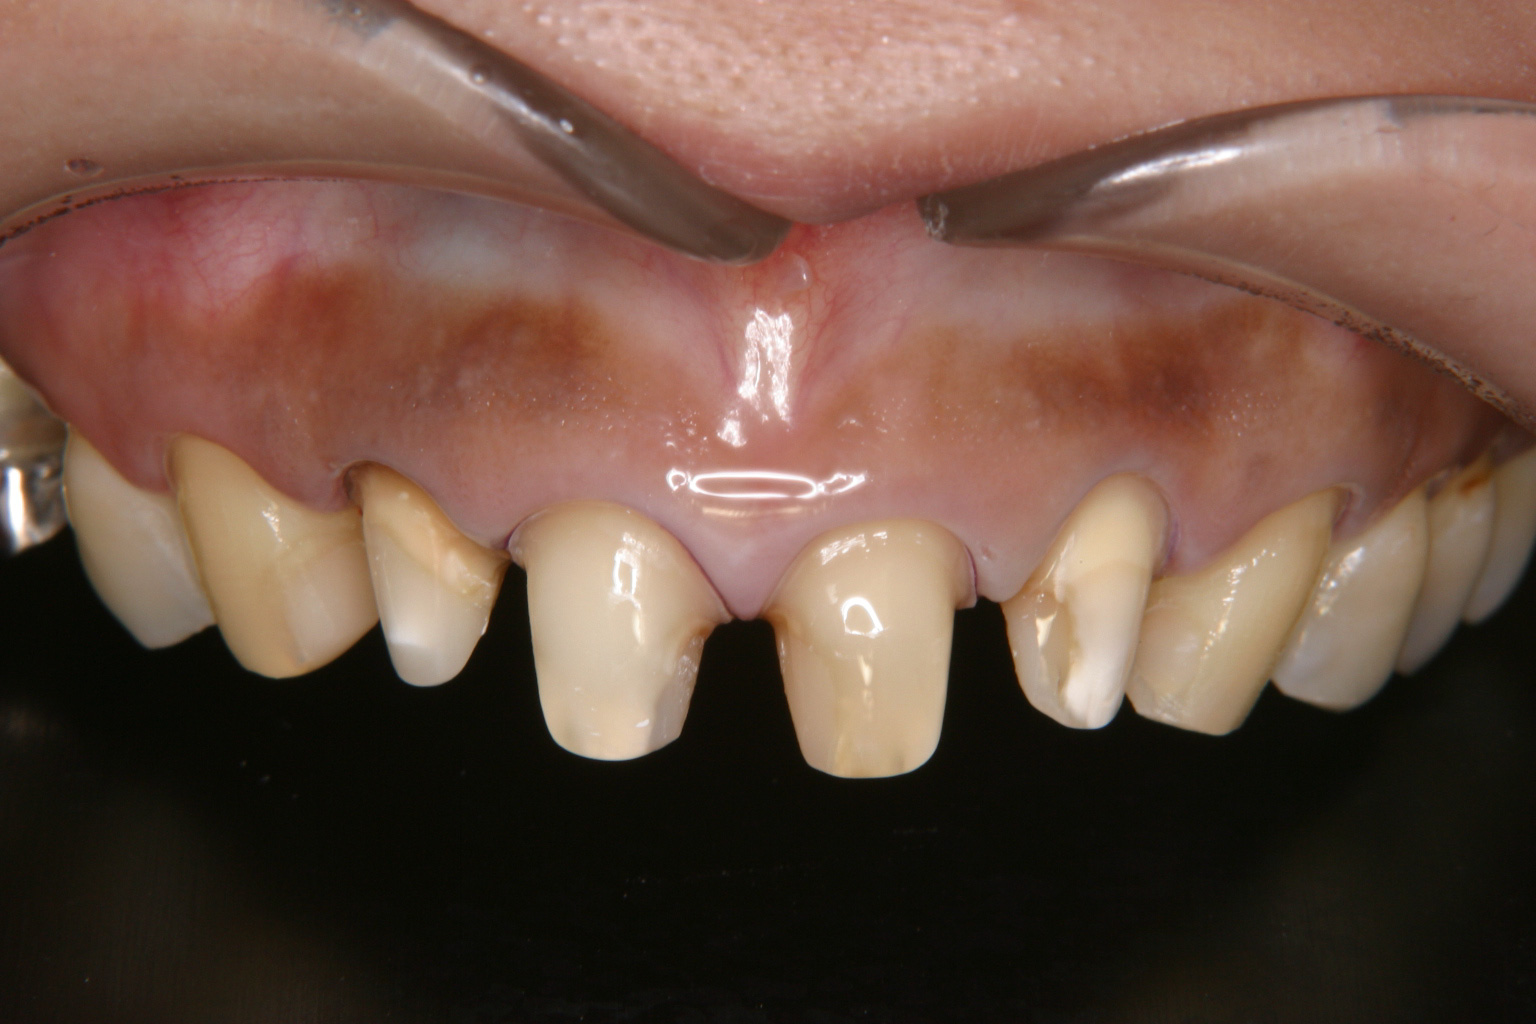

20才代の女性で、職業は雑誌のモデルである。

上顎前歯部の審美障害を主訴に来院。4前歯は失活しており、右側切歯は唇側に傾斜していた(Before)。クライアントは形態的のみならず、色調の改善も含めて前歯部の審美回復を希望しており、両犬歯はラミネートベニア、4前歯はオールセラミックスクラウンによる修復を行うこととした(After)。

オールセラミックスクラウンの施術に先立ち、4前歯はファイバーポストを植立し、オールセラミックスの特徴を最大限に生かすように配慮した。両犬歯は側方ガイドを変えないためにも舌面形態に変更を与えることのない、ラミネートベニアにて審美回復を行った。